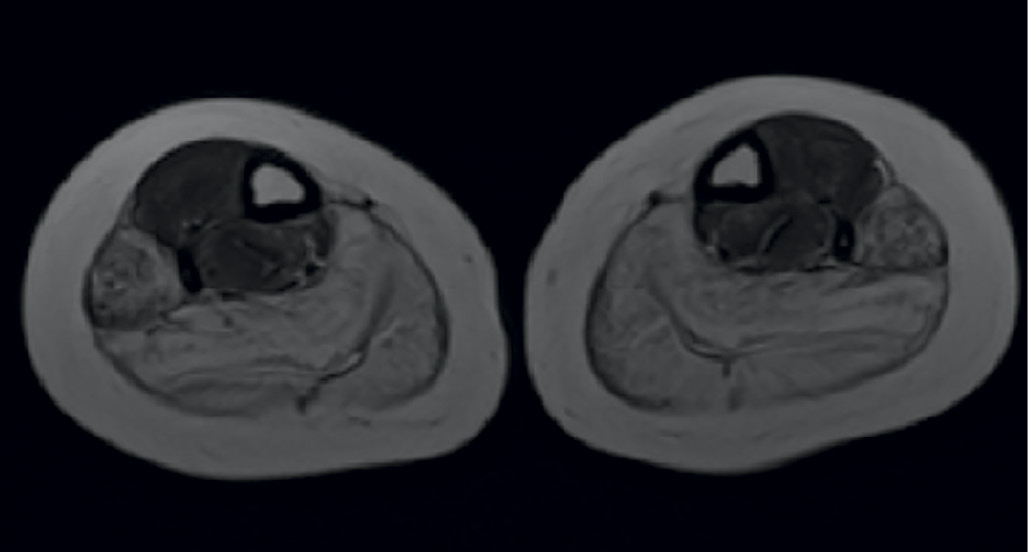

Для картины МРТ верхних и нижних конечностей характерны поражение ягодичных и большой приводящей мышц, бицепса бедра, а также дельтовидной мышцы и двуглавой мышцы руки (рис. 3) [18].

Рис. 3. МРТ мышц.